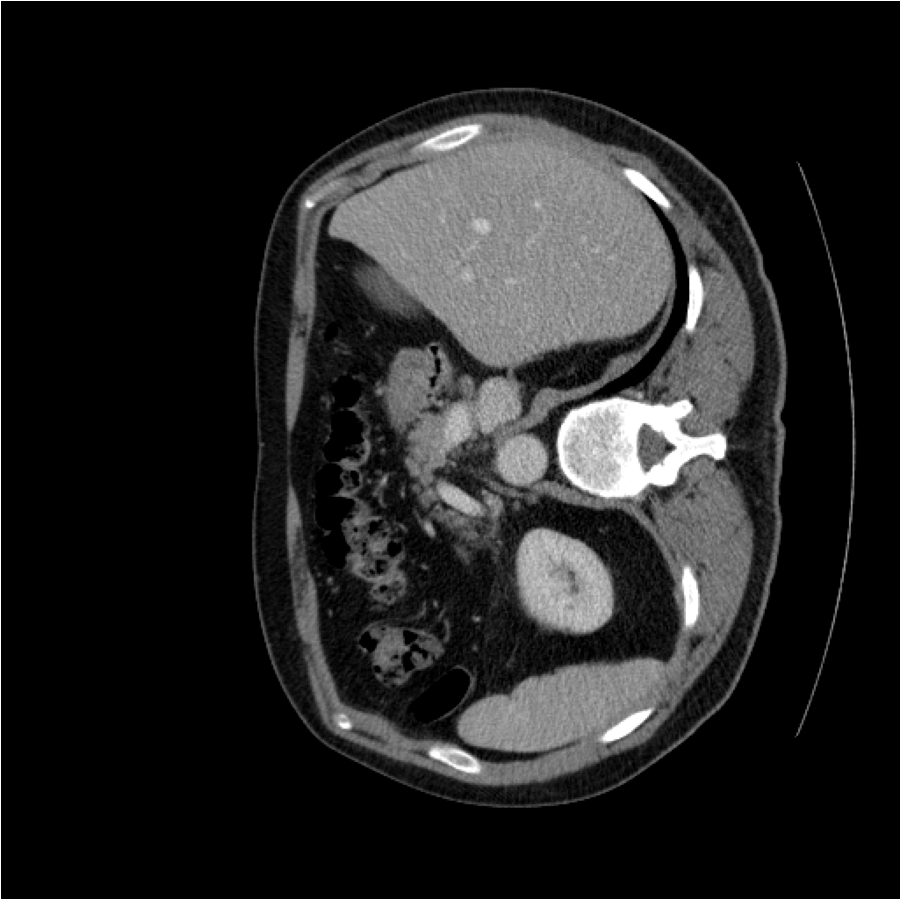

The evaluation process uses a variety of medical image datasets in different modalities, including the ISIC 2017 T1 dataset with camera images of skin lesions [79], the GlaS dataset of gland images under the microscope [80], and the MoNuSeg dataset of nuclear images under the microscope [81]. All of the above datasets are intended for binary segmentation. In addition, the Synapse dataset of CT images is also used for multi-label organ segmentation. The BraTS2018 dataset 111https://www.med.upenn.edu/sbia/BraTS2018/data.html, consisting of magnetic resonance imaging (MRI) data, is used for the purpose of multimodal segmentation of brain tumors. The ISIC 2017 Task 1 dataset contains 2,000 images for training, 150 images for validation and 600 images for testing. The MoNuSeg dataset contains 30 training images and 14 test images, while the GlaS dataset contains 85 training images and 80 test images. According to the setting in [76], the Synapse dataset consists of two subsets: the training dataset with 18 cases and the validation dataset with 12 cases, resulting in a total of 2212 axial slices. The BraTS2018 challenge training data comprises 285 multimodal 3D MRI scans, including 210 MRI scans from subjects with higher grade glioma (HGG) and 75 scans from subjects with lower grade glioma (LGG). The 3D MRI images have a volume dimension of 240×240×155240\times{240}\times{155}. They describe four MRI modalities: native (T1), post-contrast T1-weighted (T1Gd), T2-weighted (T2) and T2 Fluid Attenuated Inversion Recovery (FLAIR) volumes. The tumor segmentation consists of dividing the tumor into three distinct sub-regions: the whole tumor (WT), the tumor core (TC) and the enhancing tumor (ET). The dataset was first split into a training and validation set comprising 80%80\% of the data and a test set comprising 20%20\% of the data. Subsequent images were extracted into 2D image slices in accordance with Kermi et al. [82].

Figure 4: (a)(b)(f)(g) Training images; (c)(d)(e)(h)(i)(j) Generated augmented images with outlined superpixel grids in green color. The numbers of superpixels, l1l_{1} and l2l_{2} corresponding to either training image, are fixed here for visualization.

In general, increasing the number of superpixel, ll, leads to a finer granularity that provides less semantic information but more contour information. Conversely, decreasing in the superpixel number results in a coarser granularity that provides less contour information but more semantic information. As can be seen in Figure 4, the superpixels in Figure 4(c) and Figure 4(h) have a higher level of semantic information but lower capacity of contour information when the superpixel number, denoted by ll, is relatively small. In Figures 4(e) and 4(j), the number of superpixels, ll, is relatively large. Consequently, although the synthetic superpixel maps have detailed boundaries, they lack semantics. For images with a large amount of fine-grained content or granularity, it is recommended to use a relatively large number of superpixels, where each superpixel is relatively small. Conversely, a small number of superpixels can also be used, with each superpixel being relatively large. In our method, the number of superpixels ll for each image is randomly determined according to a uniform distribution lU(lmin,lmax)l\sim U(l_{min},l_{max}) instead of setting it as constant. This is easier to tune and can increase the diversity of the augmentation space. It can also improve the robustness of our method. The quantitative analysis is shown in Table 8.